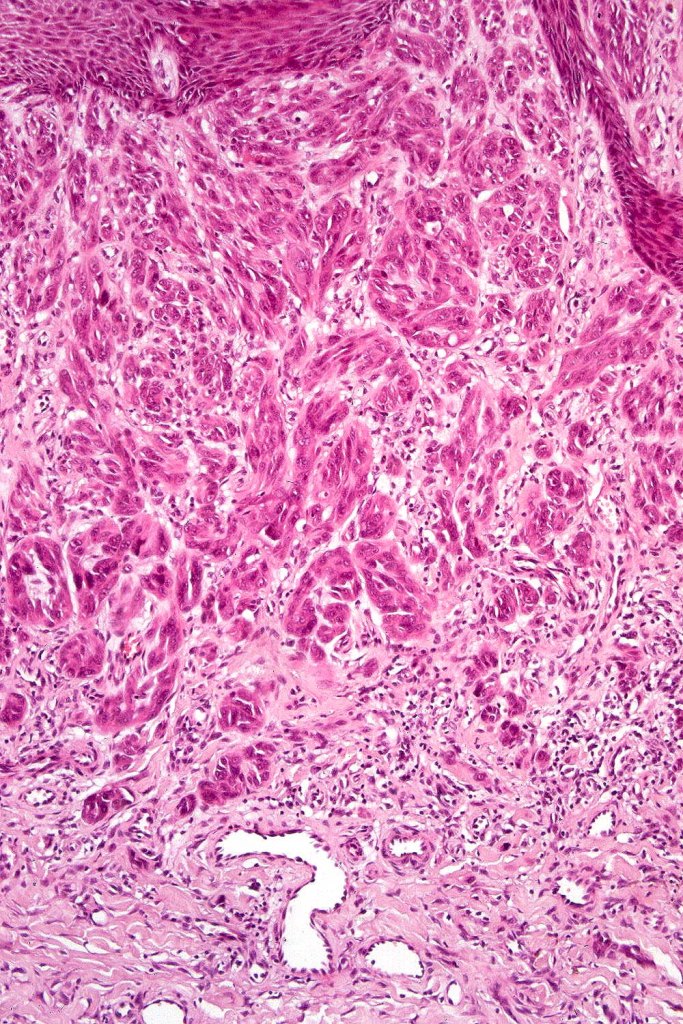

•Junctional nests often vertically orientated, dyscohesive with a surrounding retraction artifact

•Pleomorphism is almost invariable but affects all of the population to the same extent i.e., the cells & nuclei all look very much the same

•Spindle cell nests often display a “raining down” growth pattern

•Spindle cells have abundant cytoplasm and vesicular nuclei with small nucleoli

•Epithelioid cell variants often show greater pleomorphism and cells can frequently appear bizarre with abundant, sometimes ground glass cytoplasm and large vesicular nuclei with prominent eosinophilic nucleoli, multinucleate cells are often seen

•Intracytoplasmic pseudoinclusions commonly present in epithelioid cells

•Kamino bodies (often multiple) are a characteristic feature

•Lymphocytic infiltration at the base of the lesion